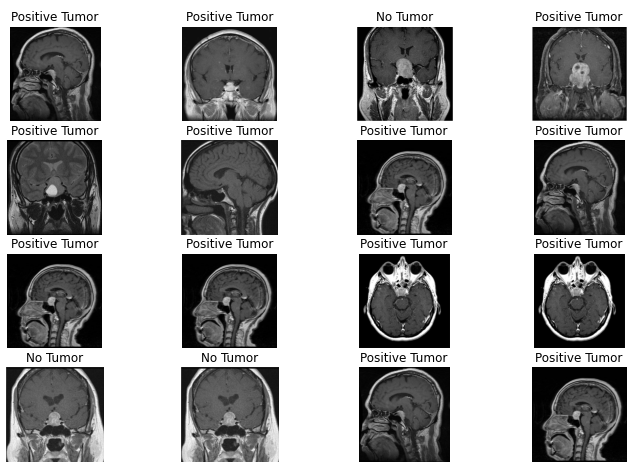

Finally, it is the time to examine the results.